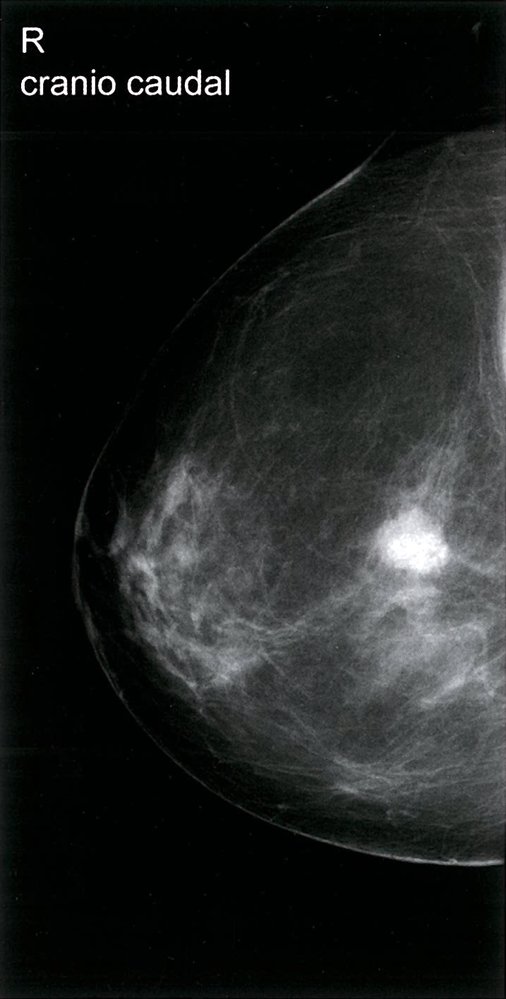

Screening mammography

• Mammography performed in asymptomatic individuals for early identification and management of breast cancer.

• Typically limited to bilateral craniocaudal and mediolateral oblique views of the breast.

• Additional views or digital breast tomosynthesis may be performed to improve visualization of breast tissue if necessary.

Diagnostic mammography

• Mammography performed to evaluate concerning breast symptoms (e.g., breast mass, focal pain, nipple discharge) or to further evaluate abnormalities detected on screening mammography or breast MRI.

• In addition to craniocaudal and mediolateral views, supplemental views (e.g., spot compression with magnification) with or without digital breast tomosynthesis may be performed to improve visualization of breast abnormalities.